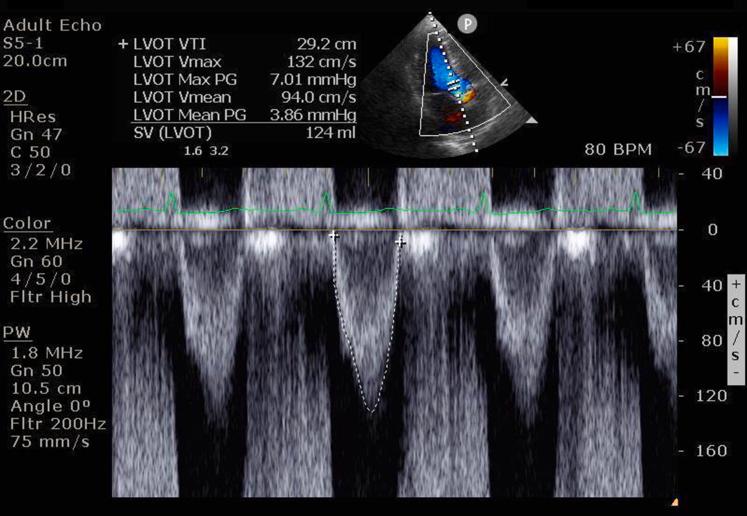

A 38-year-old pregnant patient was managed by the cardio-obstetrics multidisciplinary team for severe degenerative bioprosthetic aortic valve failure. She was medically managed utilizing echocardiogram and brain natriuretic peptide until she demonstrated worsening heart failure. A valve and cardio-obstetrics team evaluation led to valve-in-valve transcatheter aortic valve replacement at 30 weeks' gestation.

一名38岁的孕妇由心脏妇产科多学科团队负责治疗严重的退行性生物人工主动脉瓣功能衰竭。在她出现心力衰竭恶化之前,一直通过超声心动图和脑钠肽进行药物治疗。瓣膜和心脏妇产科团队评估后,在妊娠30周时为她进行了经导管主动脉瓣置换术(瓣中瓣)。